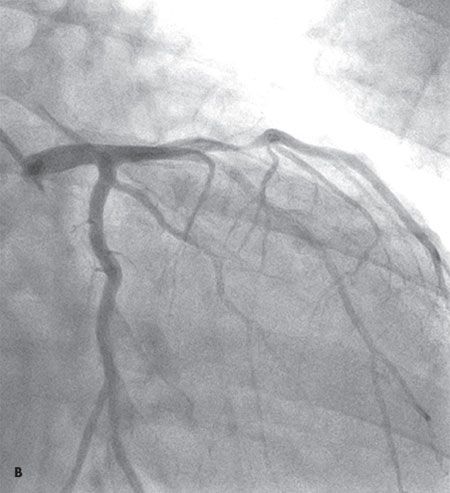

Coronary arteriography revealed single-vessel disease with a 90% stenosis of the proximal left anterior descending (LAD) artery (B). Ejection fraction was 50%. The patient received a drug-eluting stent to the LAD artery lesion and was discharged home the following day in good condition.